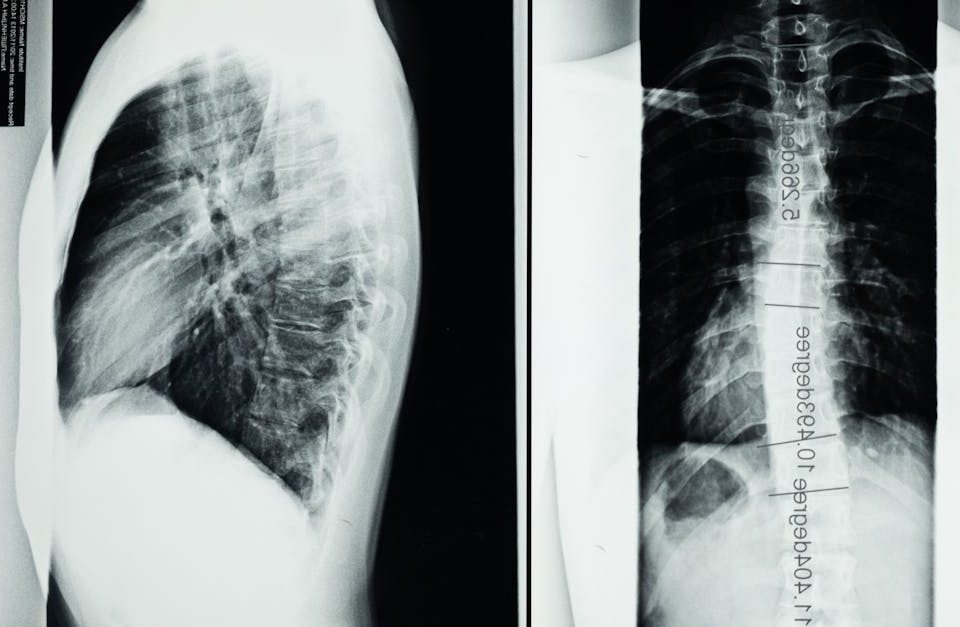

Dans cette catégorie, découvrez une solution avancée et non invasive pour traiter la sténose foraminale, une condition souvent associée à des douleurs chroniques, des engourdissements et une mobilité réduite. La décompression neurovertébrale cible spécifiquement les zones de compression dans les foramens vertébraux, soulageant la pression exercée sur les nerfs et favorisant la régénération des tissus. Nos articles expliquent comment cette technique de pointe peut réduire efficacement la douleur, améliorer la qualité de vie et prévenir la progression de la condition. Soutenue par des données scientifiques, cette approche constitue une alternative sécuritaire et efficace aux interventions chirurgicales, intégrée dans une stratégie globale de gestion des douleurs vertébrales.

Sténose foraminale